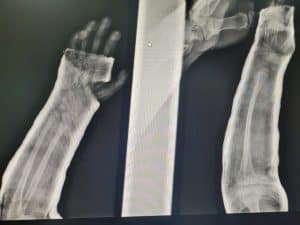

- Fracturas de antebrazo

- Fractura de radio y cubito

Fractura radiocubital

Fractura de radio distal